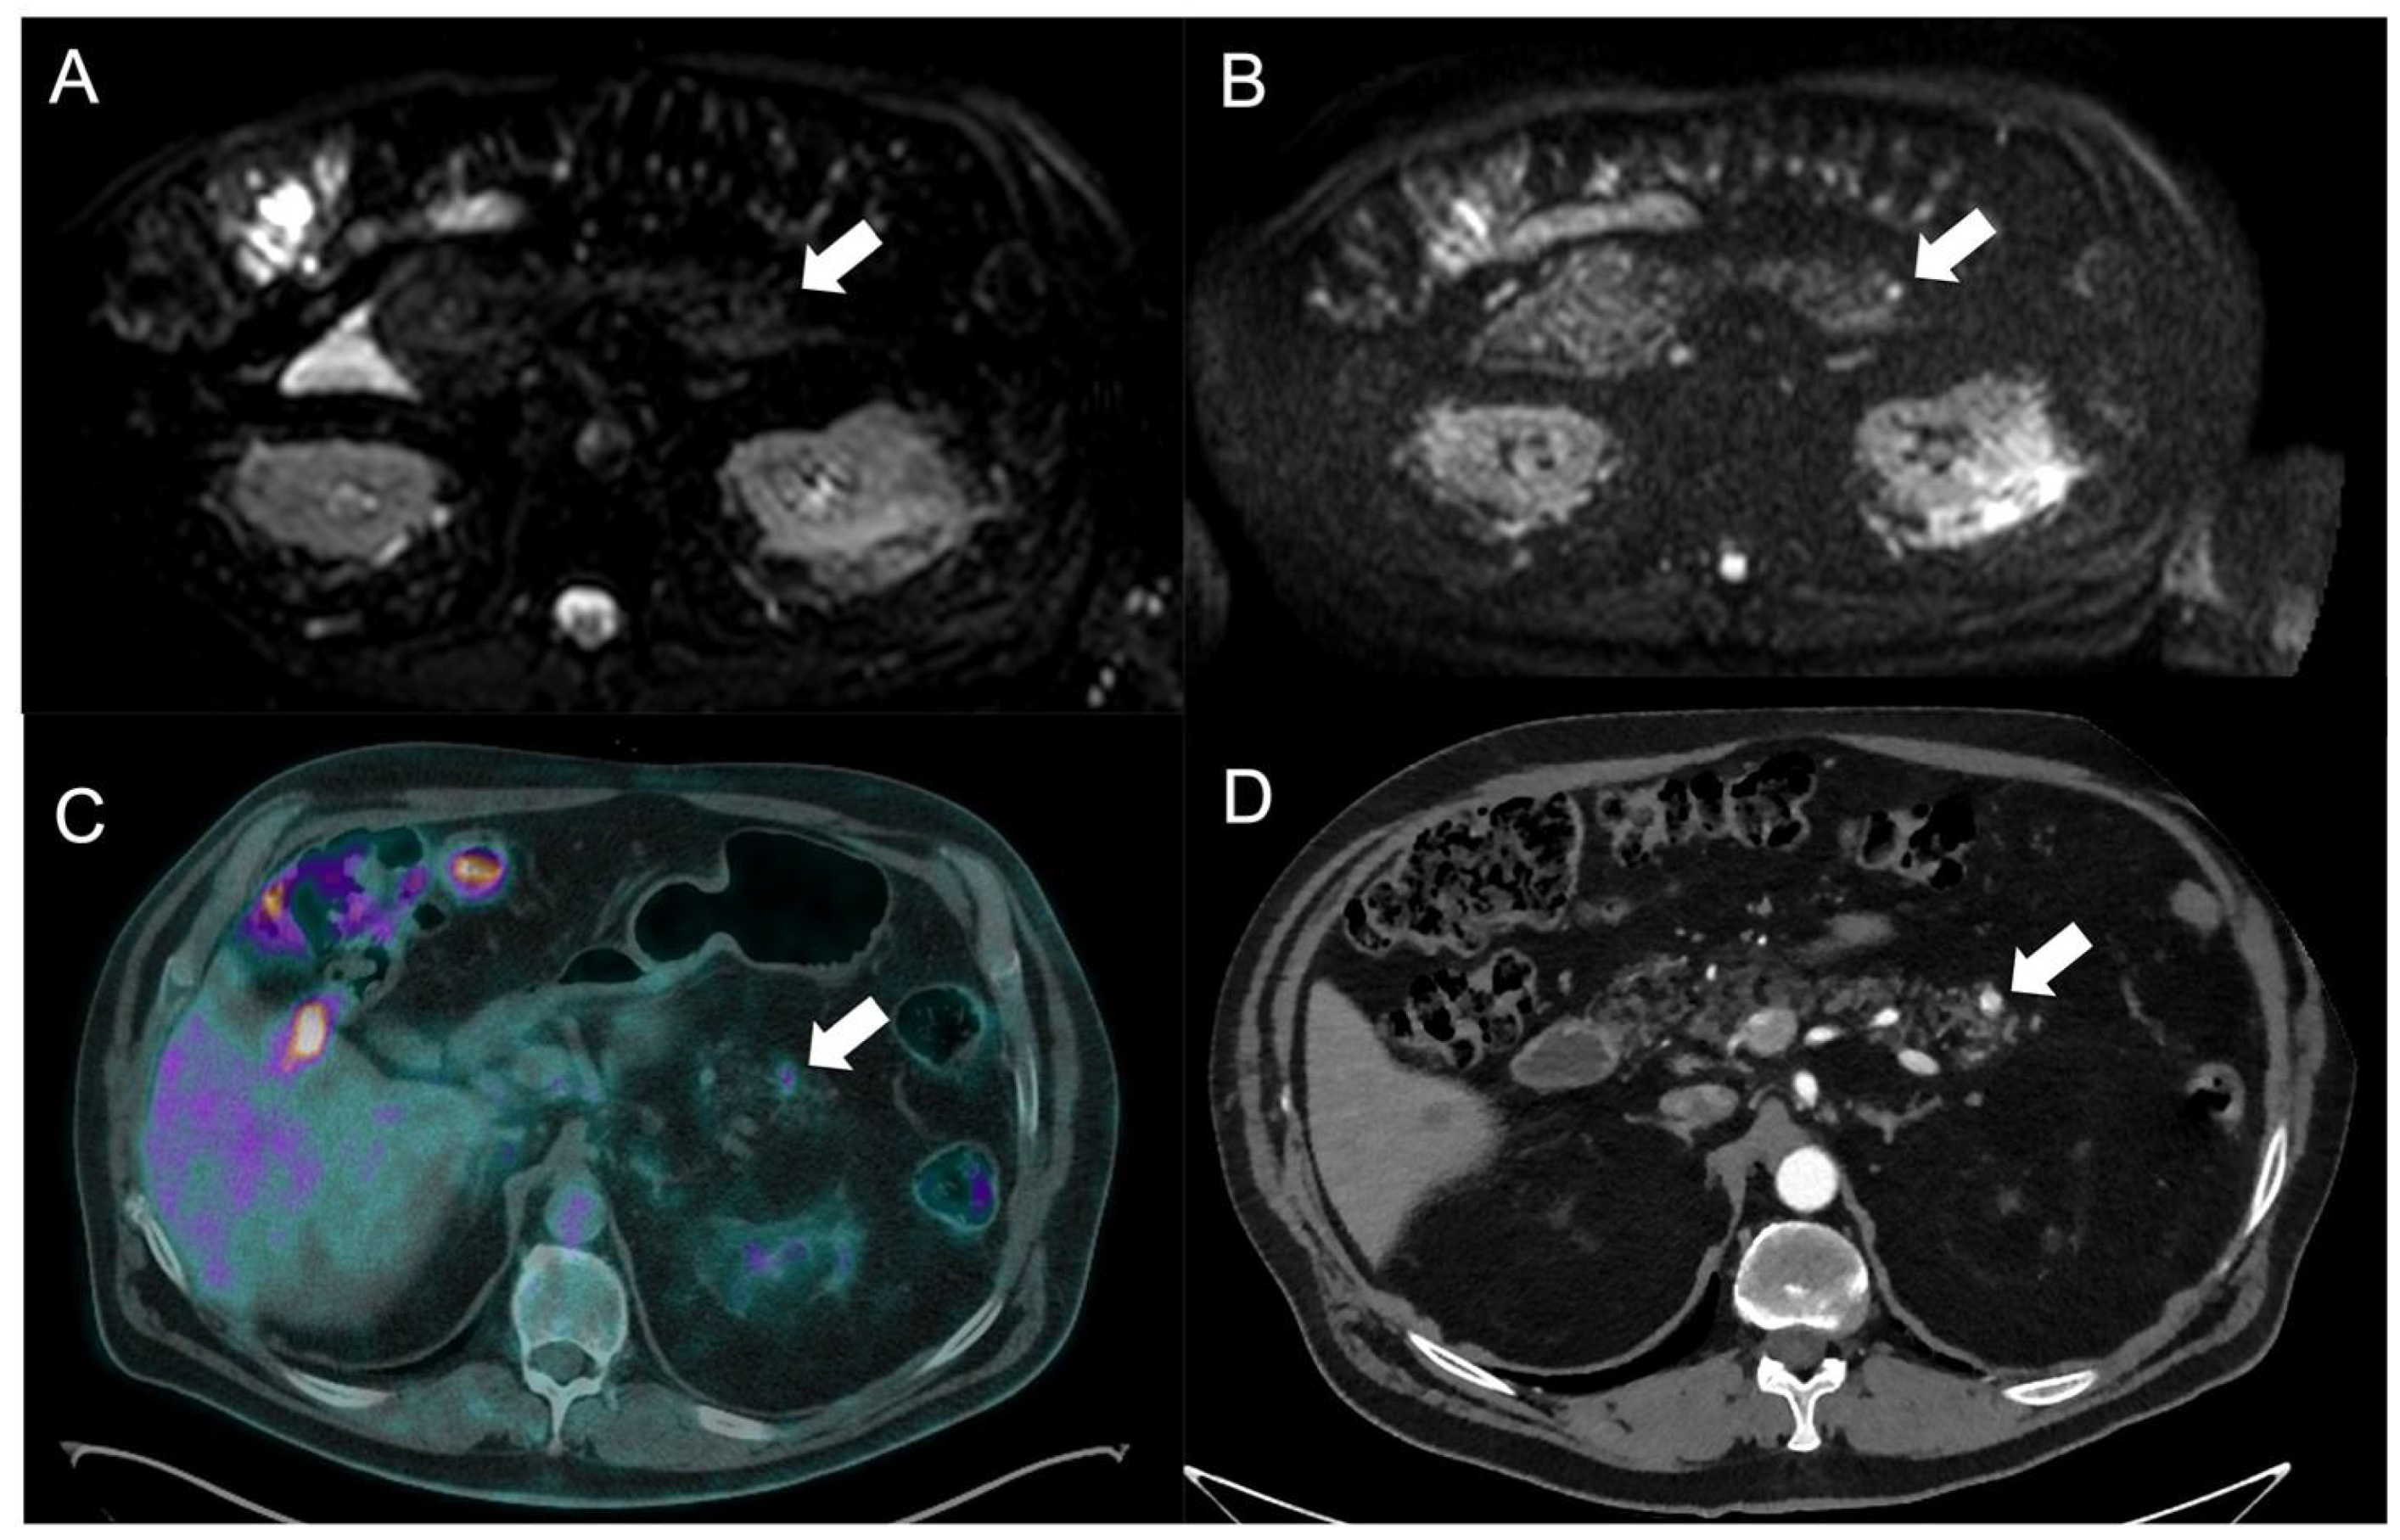

- Schmid-Tannwald, C.; Schmid-Tannwald, C.; Morelli, J.; Neumann, R.; Haug, A.; Jansen, N.; Nikolaou, K.; Schramm, N.; Reiser, M.; Rist, C. Comparison of abdominal MRI with diffusion-weighted imaging to 68Ga-DOTATATE PET/CT in detection of neuroendocrine tumors of the pancreas. Eur. J. Nucl. Med. Mol. Imag. 2013, 40, 897–907. [Google Scholar] [CrossRef]

- Brenner, R.; Metens, T.; Bali, M.; Demetter, P.; Matos, C. Pancreatic neuroendocrine tumor: Added value of fusion of T2-weighted imaging and high b-value diffusion-weighted imaging for tumor detection. Eur. J. Radiol. 2012, 81, e746–e749. [Google Scholar] [CrossRef] [PubMed]